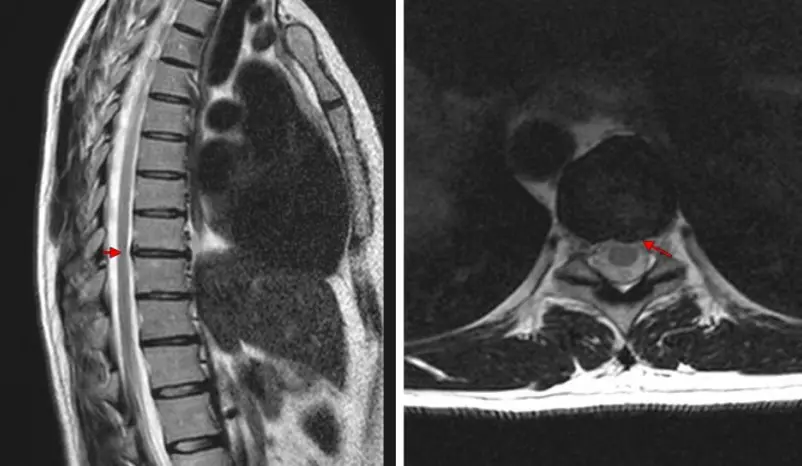

أظهر مخطط كهربية القلب أن كل شيء على ما يرام بالنسبة للقلب. لقد خضعت لفحص كامل في المستشفى ووجدت ذلك لدي داء عظمي غضروفي صدري. لم أتوقع هذا! أمارس الرياضة وأمارس اليوغا وأنام على مرتبة طبية. كله عبثا...